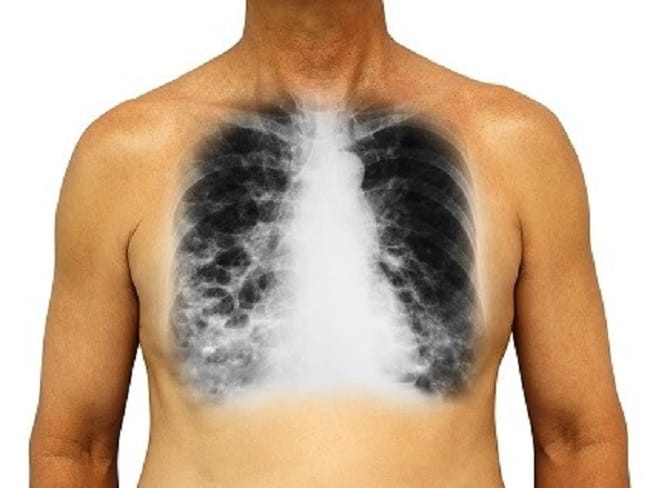

- Rontgen atau CT scan pada paru-paru, untuk melihat kondisi paru-paru dan saluran pernapasan secara detail